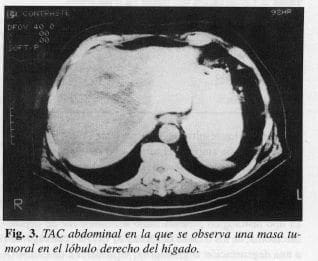

Paciente de 51 años, de sexo masculino, quien ingresa al servicio de cirugía para exámenes rutinarios. Refiere dolor ocasional de tipo opresivo en el hipocondrio derecho. Se realiza una ecografía abdominal y una TAC que confirman una masa de 15 cm aproximadamente, que compromete el lóbulo derecho del hígado (Fig. 3).

El paciente es llevado a cirugía, se practica biopsia cuyo examen mostró hepatocarcinoma. La masa tumoral hallada, compromete el lóbulo derecho del hígado en su totalidad e infiltra el lóbulo izquierdo. La resección en cuña practicada, ocasiona sangrado profuso del tumor por necrosis extensa, generalizada, en su interior. El sangrado logra ser controlado, finalmente, por medio de taponamiento con compresas y el paciente es llevado a la DCI para recuperación hemodinámica.